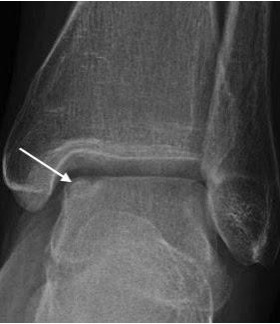

OSTEOCHONDRITIS DISSECANS

- Most common in children / adolescents

- Due to poor blood flow to subchondral bone

- Partial or complete detachment of an osteochondral fragment

- Usually involves the medial talar dome

- ‘Subchondral halo’ outlines the osteochondral fragment

- Focal flattening and compression of talar dome; osteochondral fragment within crater

- Displaced osteochondral fragment with focal concavity of talar dome and intra-articular bone fragment

Osteochondritis dissecans medial talar dome (arrow)